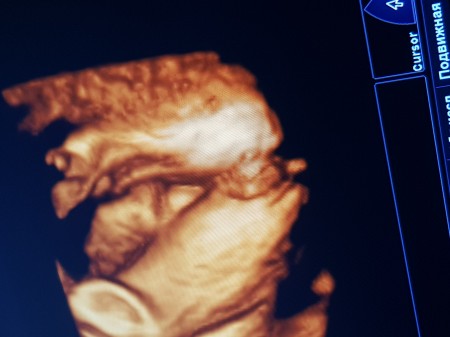

Cinsiyyet kızmı erkekmi?tahin edermisiniz?

Gebelik haftası 31

Erkek büyük ihtimalle canım. Doktorun birşey demedi mi?

Doktoeum gah kız gah erkek didi çunki tam gpstermiyor bende bunu telüfonla cekib evde vaknca aaa vu erkek duye duşundum

Erkeğe benziyor sanki skrotum bezleri olusmus gibi kiz organina cok benzetemedim

Kiza benzettim sanki ama hayirlisi olsun 31 haftalik olmussun blmiyomusun cinsiyetini

31 haftalikken erekekk oldunu biliyon ama bide bu resimi atıyon diyim yüzde yüz erkek

Bence kız canım benimde böyle bı ultrason fotoğrafım var doktor o pipi gibi görünen şeye omuriliğin başladığı yer demişti yanlış hatırlamıyorsam